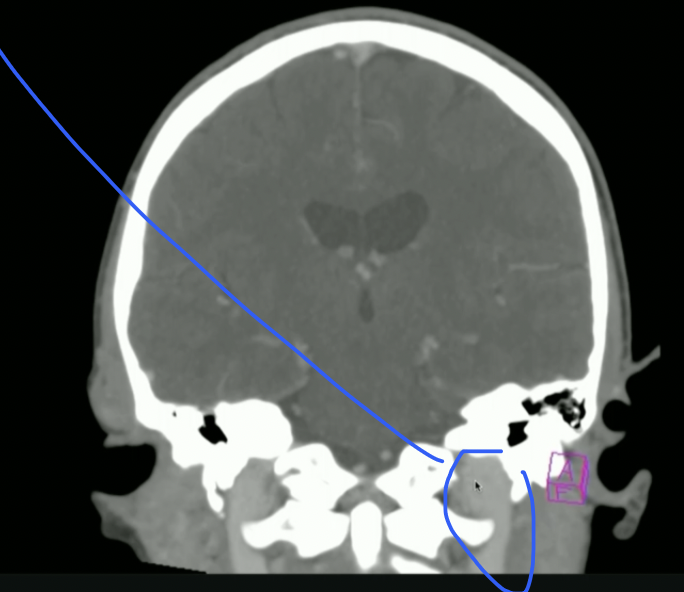

<p>What is Top + Bottom Circle + Arrow?</p>

What is Top + Bottom Circle + Arrow?

• Top: 3rd Ventricle

• Bottom: 4th Ventricle

• Arrow: Cerebral Aqueduct